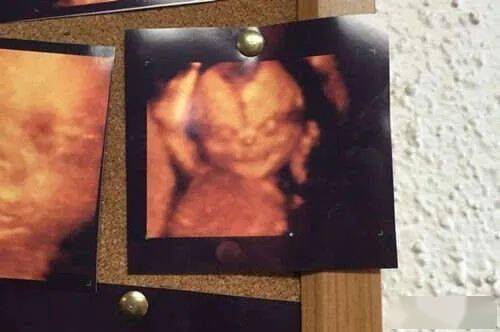

一位肠道疼痛的女性觉得自己长了肿瘤,去医院看急诊时医生在核磁共振的报告中,看到她的肠道里竟然有一个6个月大的婴儿???

示意图

报告显示,女患者胃肠道附近的腹腔中有一个近6个月大的胎儿,而且胎儿还在不断生长!